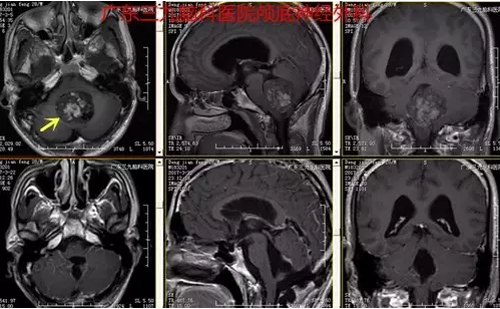

图4:术后术后磁共振提示肿瘤全切

此例患者由于肿瘤位于后颅窝,离脑干较近,因此手术全切存在一定的风险。但是过多的肿瘤残余将导致预后较差, 因此在不增加手术风险和并发症的前提下应尽可能多切除肿瘤。本例患者手术过程短,术后恢复快,未有明确并发症,术后复查头颅MR提示肿瘤全切。